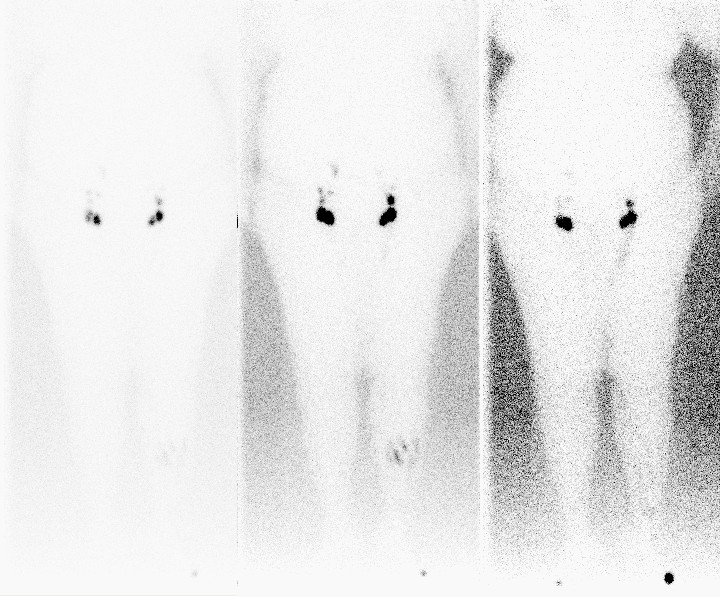

![Lymfeklierscintigrafie (click on photo to enlarge) [source: www.huidziekten.nl] Lymfeklierscintigrafie](../../../images/lymfscintigrafie1z.jpg) |

![Lymfeklierscintigrafie (click on photo to enlarge) [source: www.huidziekten.nl] Lymfeklierscintigrafie](../../../images/lymfscintigrafie2z.jpg) |

| lymfklierscintigram |

lymfklierscintigram |

Normaal lymfklierscintigram: visualisatie

van één lymfvat, gelokaliseerd aan de mediale zijde van onder- en bovenbeen

aan beide zijden; visualisatie van inguinale lymfklieren binnen 30 minuten na

toediening van de activiteit; visualisatie van para-iliacale klieren, para-aortale

klieren en lever binnen 2 uur na injectie; symmetrie.

Obstructief

patroon: ontbreken van de diepe lymfbaan aan de mediale zijde

van het been; visualisatie van collateralen, subcutane pooling, dermal backflow;

verminderd aantal of verminderde activiteit in inguinale klieren of meer proximaal

gelegen klierstations in vergelijking met de niet aangedane zijde; ieder ander

links/rechts-verschil; geringe functieverschillen kunnen het best op de late

opname worden beoordeeld en met kwantificering; geen verplaatsing van activiteit

vanuit de injectieplaats;